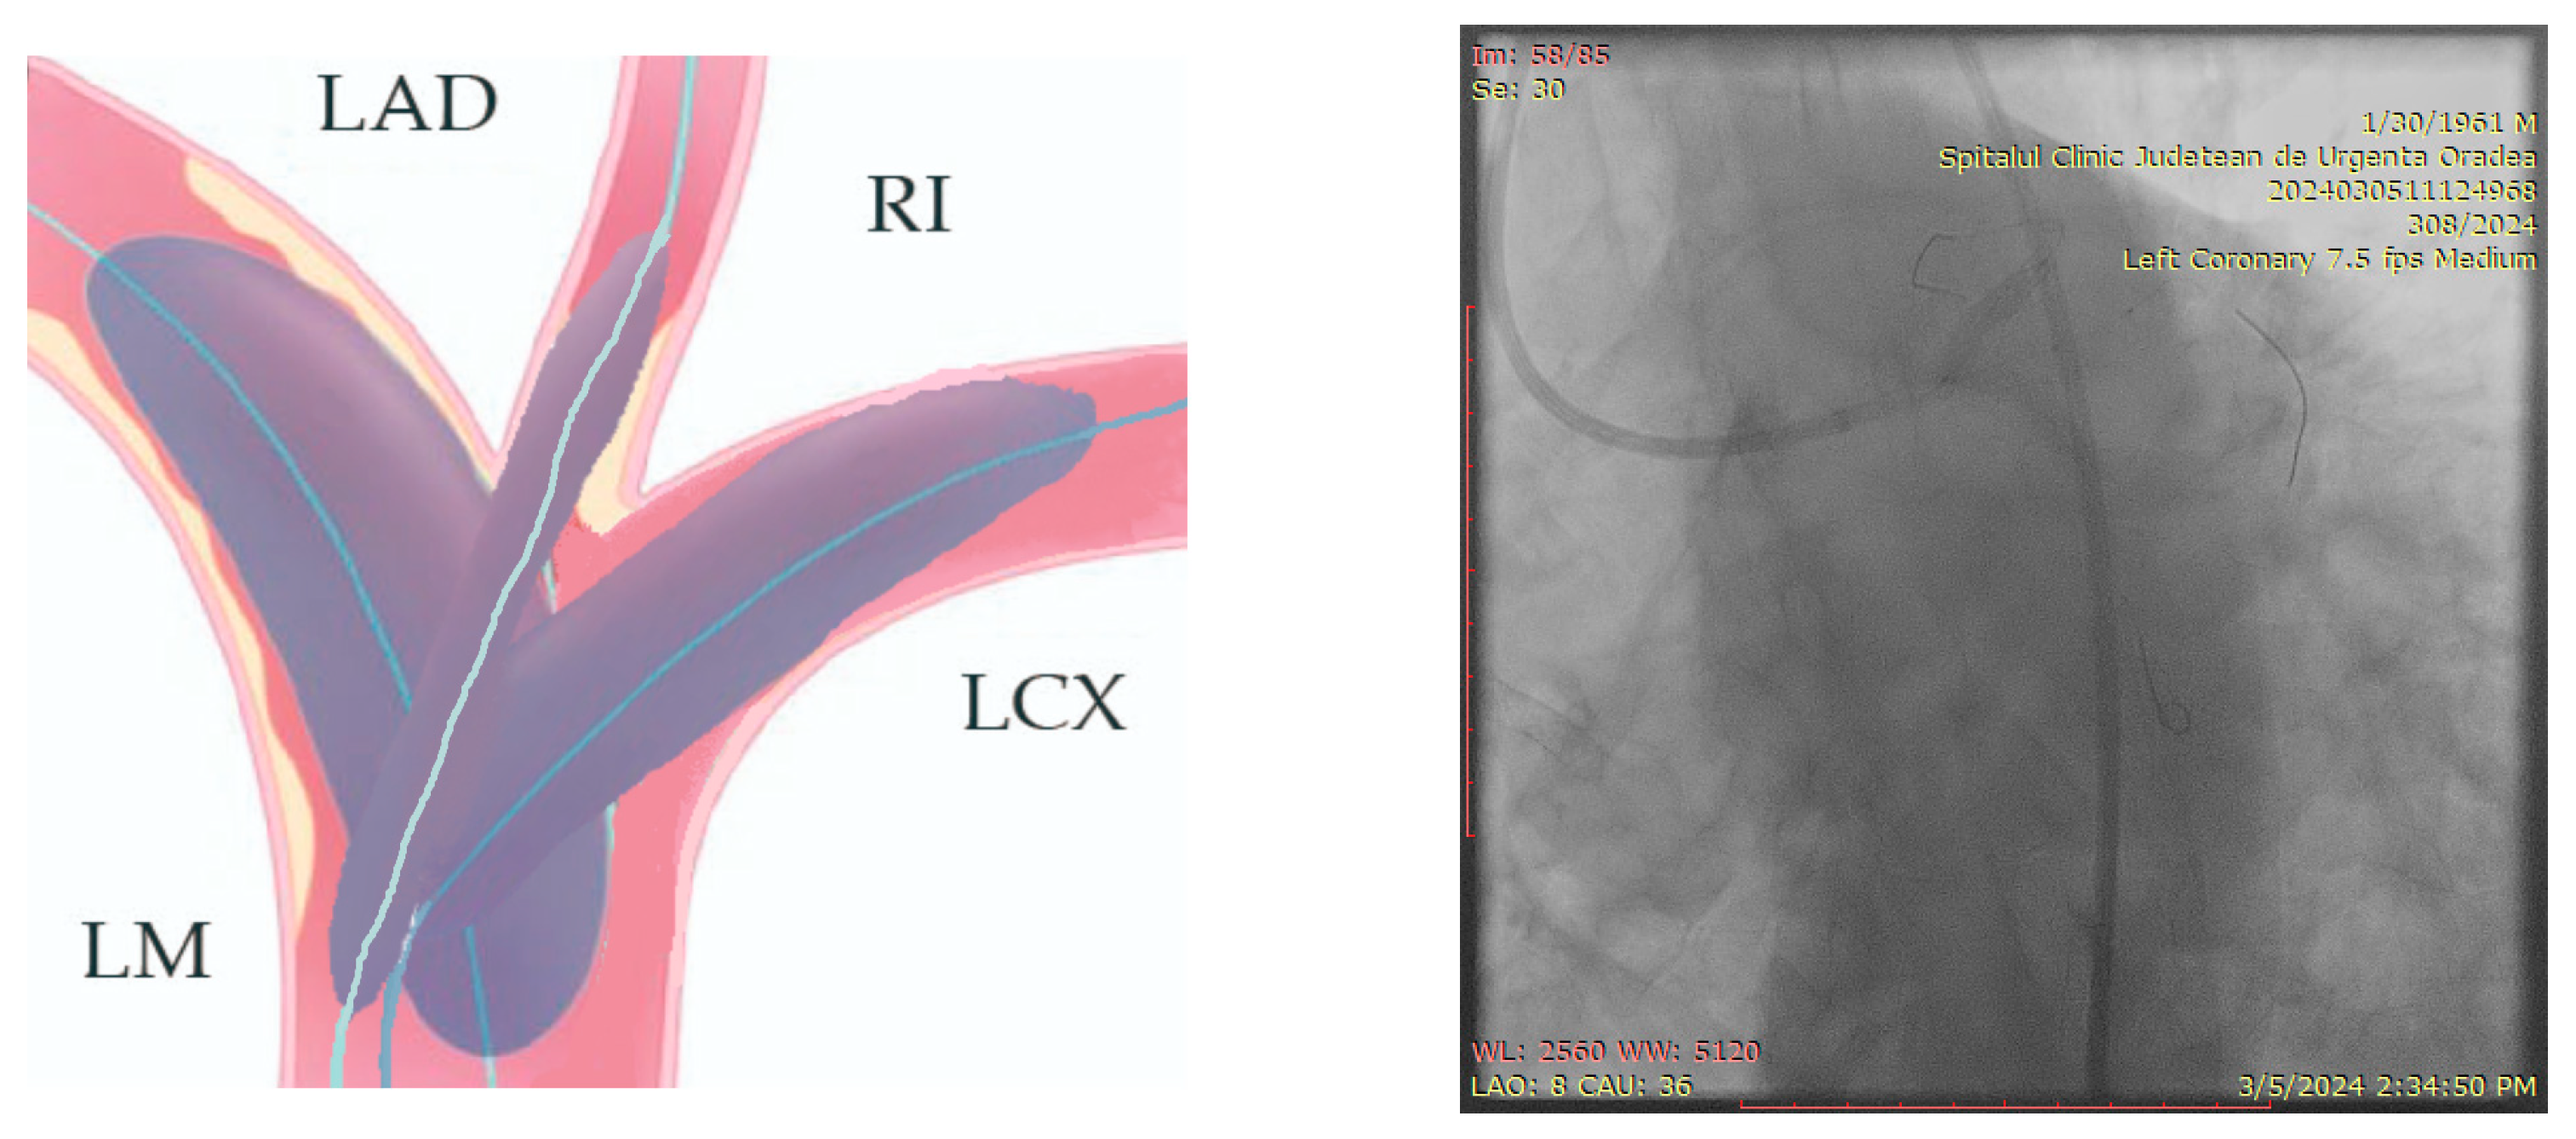

The ostium of left anterior descending artery (LAD) presented a 75% stenotic lesion, with the proximal segment displaying a 90% lesion (Figure 3). The left circumflex artery (LCX) revealed a 75% stenotic lesion of the ostium and tapered disease of its distal segment with areas of ectasic disease, with the ostium of the ramus intermedius (RI/RM) showing a 75% lesion (modified Medina classification 0-1-1-1 [4]) (Figure 4, Figure 5, Figure 6, Figure 7, Figure 8, Figure 9 and Figure 10).

Figure 3.

Left coronary artery (Right anterior oblique caudal (RAO) caudal view).

Figure 4.

Left coronary artery—LAD and LCX (LAO caudal). Red arrow and circle—ostium of LAD. Yellow arrow and square—ostium of LCX.

Figure 5.

Left coronary artery—RM(LAO caudal). Green arrow and square—ostium of RM.

Figure 6.

Left coronary artery (RAO cranial).

Figure 7.

Left coronary artery (LAO cranial).